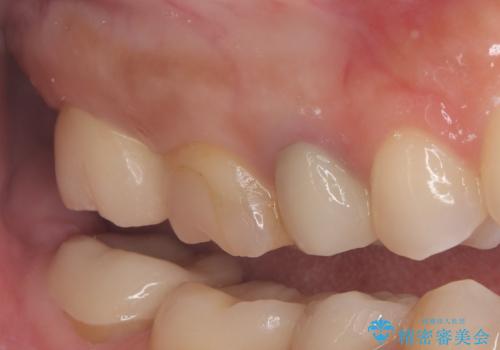

詰め物が欠けた 〈セラミッククラウン〉

もともとの修復材料とう蝕を除去し、CR裏層の上、オールセラミッククラウンにて修復しました。